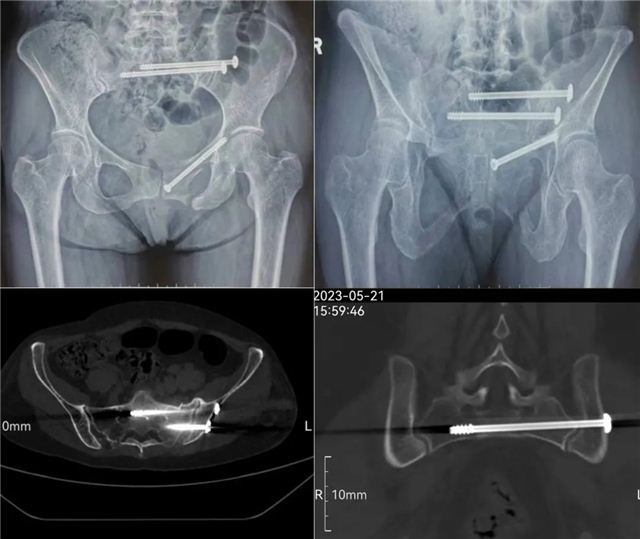

近日,长治二院创伤骨科二病区在智能骨科手术机器人辅助下,成功为两位骶骨、耻骨骨折患者实施手术。 病 例 一 术前影像 入院后,李黎明主任团队综合评估病情,为充分减少创伤,更加利于患者术后康复,决定应用更加先进、更加精准的骨科手术机器人辅助下的微创技术,为徐某行机器人辅助下骨盆骨折闭合复位内固定术。 手术过程中,李黎明主任,徐彦芳医生通过调整透视定位后将骨盆透视影像导入机器人操作界面,在该界面,根据扫描影像规划骶髂螺钉置入位置、方向、长度等数值,在导航系统引导下,经皮小切口精准置入S1,S2通道螺纹导针。经C型臂透视后证实骨折复位满意,导针位置好后,拧入规划长度的螺钉。 术后影像 病例二 术前影像 术后影像 骨科创伤二病区李黎明主任表示,智能骨科手术机器人集合了人工智能、精准手术、安全微创等特色,优势明显。特别是遇到复杂疑难的手术时,利用影像学精准建模,经过术前规划确定骨折位置,明确置入位置和角度,在术中利用灵活的机械臂进行实时定位图像导航,确保螺钉的实际置入零误差,大大降低了术中的风险。 据了解,自2021年10月“天玑”骨科手术机器人投入使用以来,我院骨科共为76名,骨折、骨伤患者成功实施了手术。